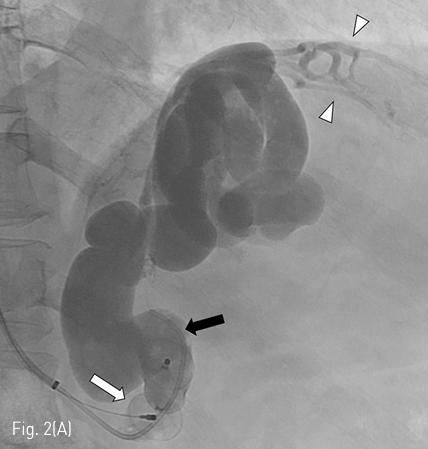

Fig 1A

(A-C) Contrast-enhanced CT images obtained before PARTO show gastric varices (black arrows) and mesenteric-retroperitoneal varices (white arrows). Arrow head indicates dilated SMV. Curved arrow indicates the meso-caval shunt.